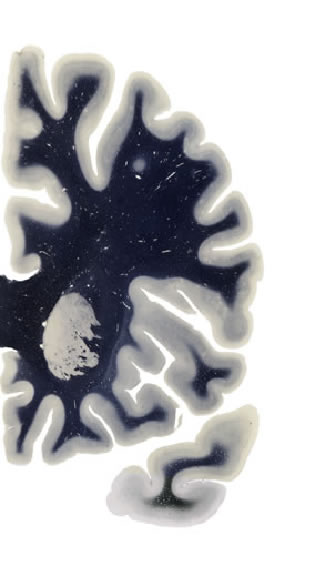

Hi-Resolution Sections · Cells (Nissl Staining) · Virtual Microscopy

Frontal sections (Nissl) from the Atlas Brain:

Slice ID:

r2-0571

Plate NR:

10

Position:

-19,1 mm